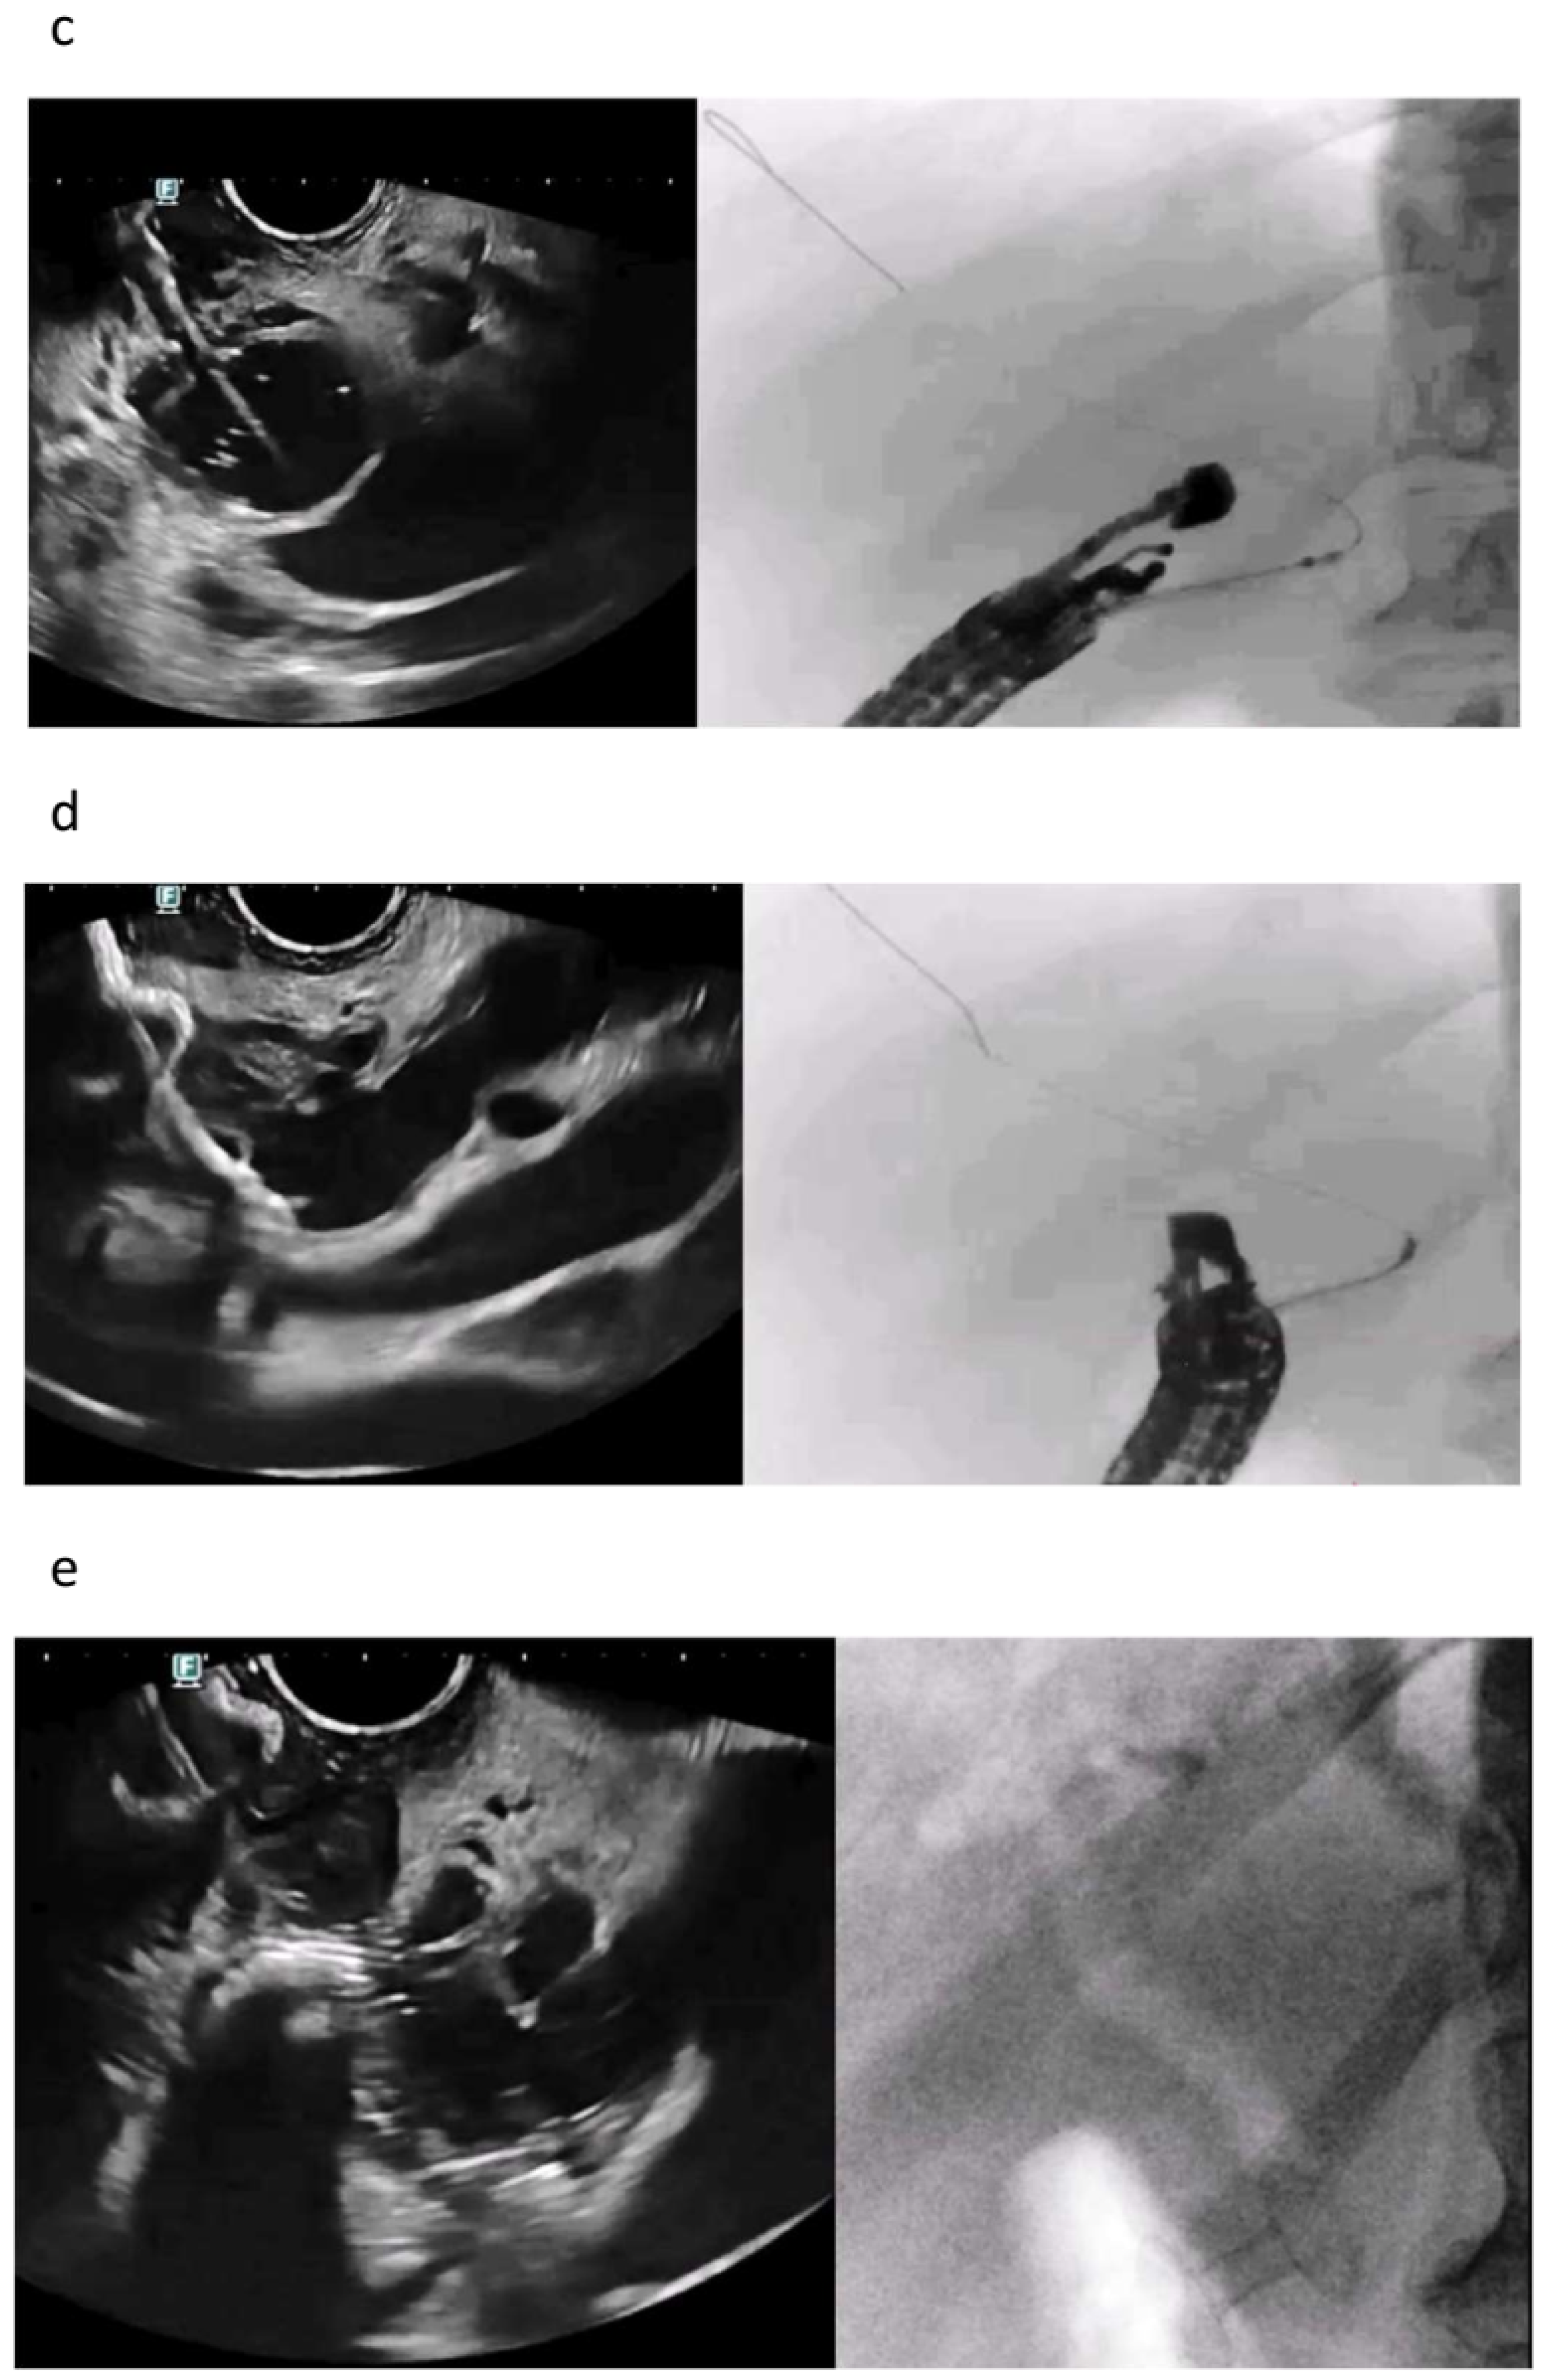

5. Rendezvous Techniques

5.1. Should Rendezvous Be Used First?

5.2. Which Rendezvous Route Should Be Used?